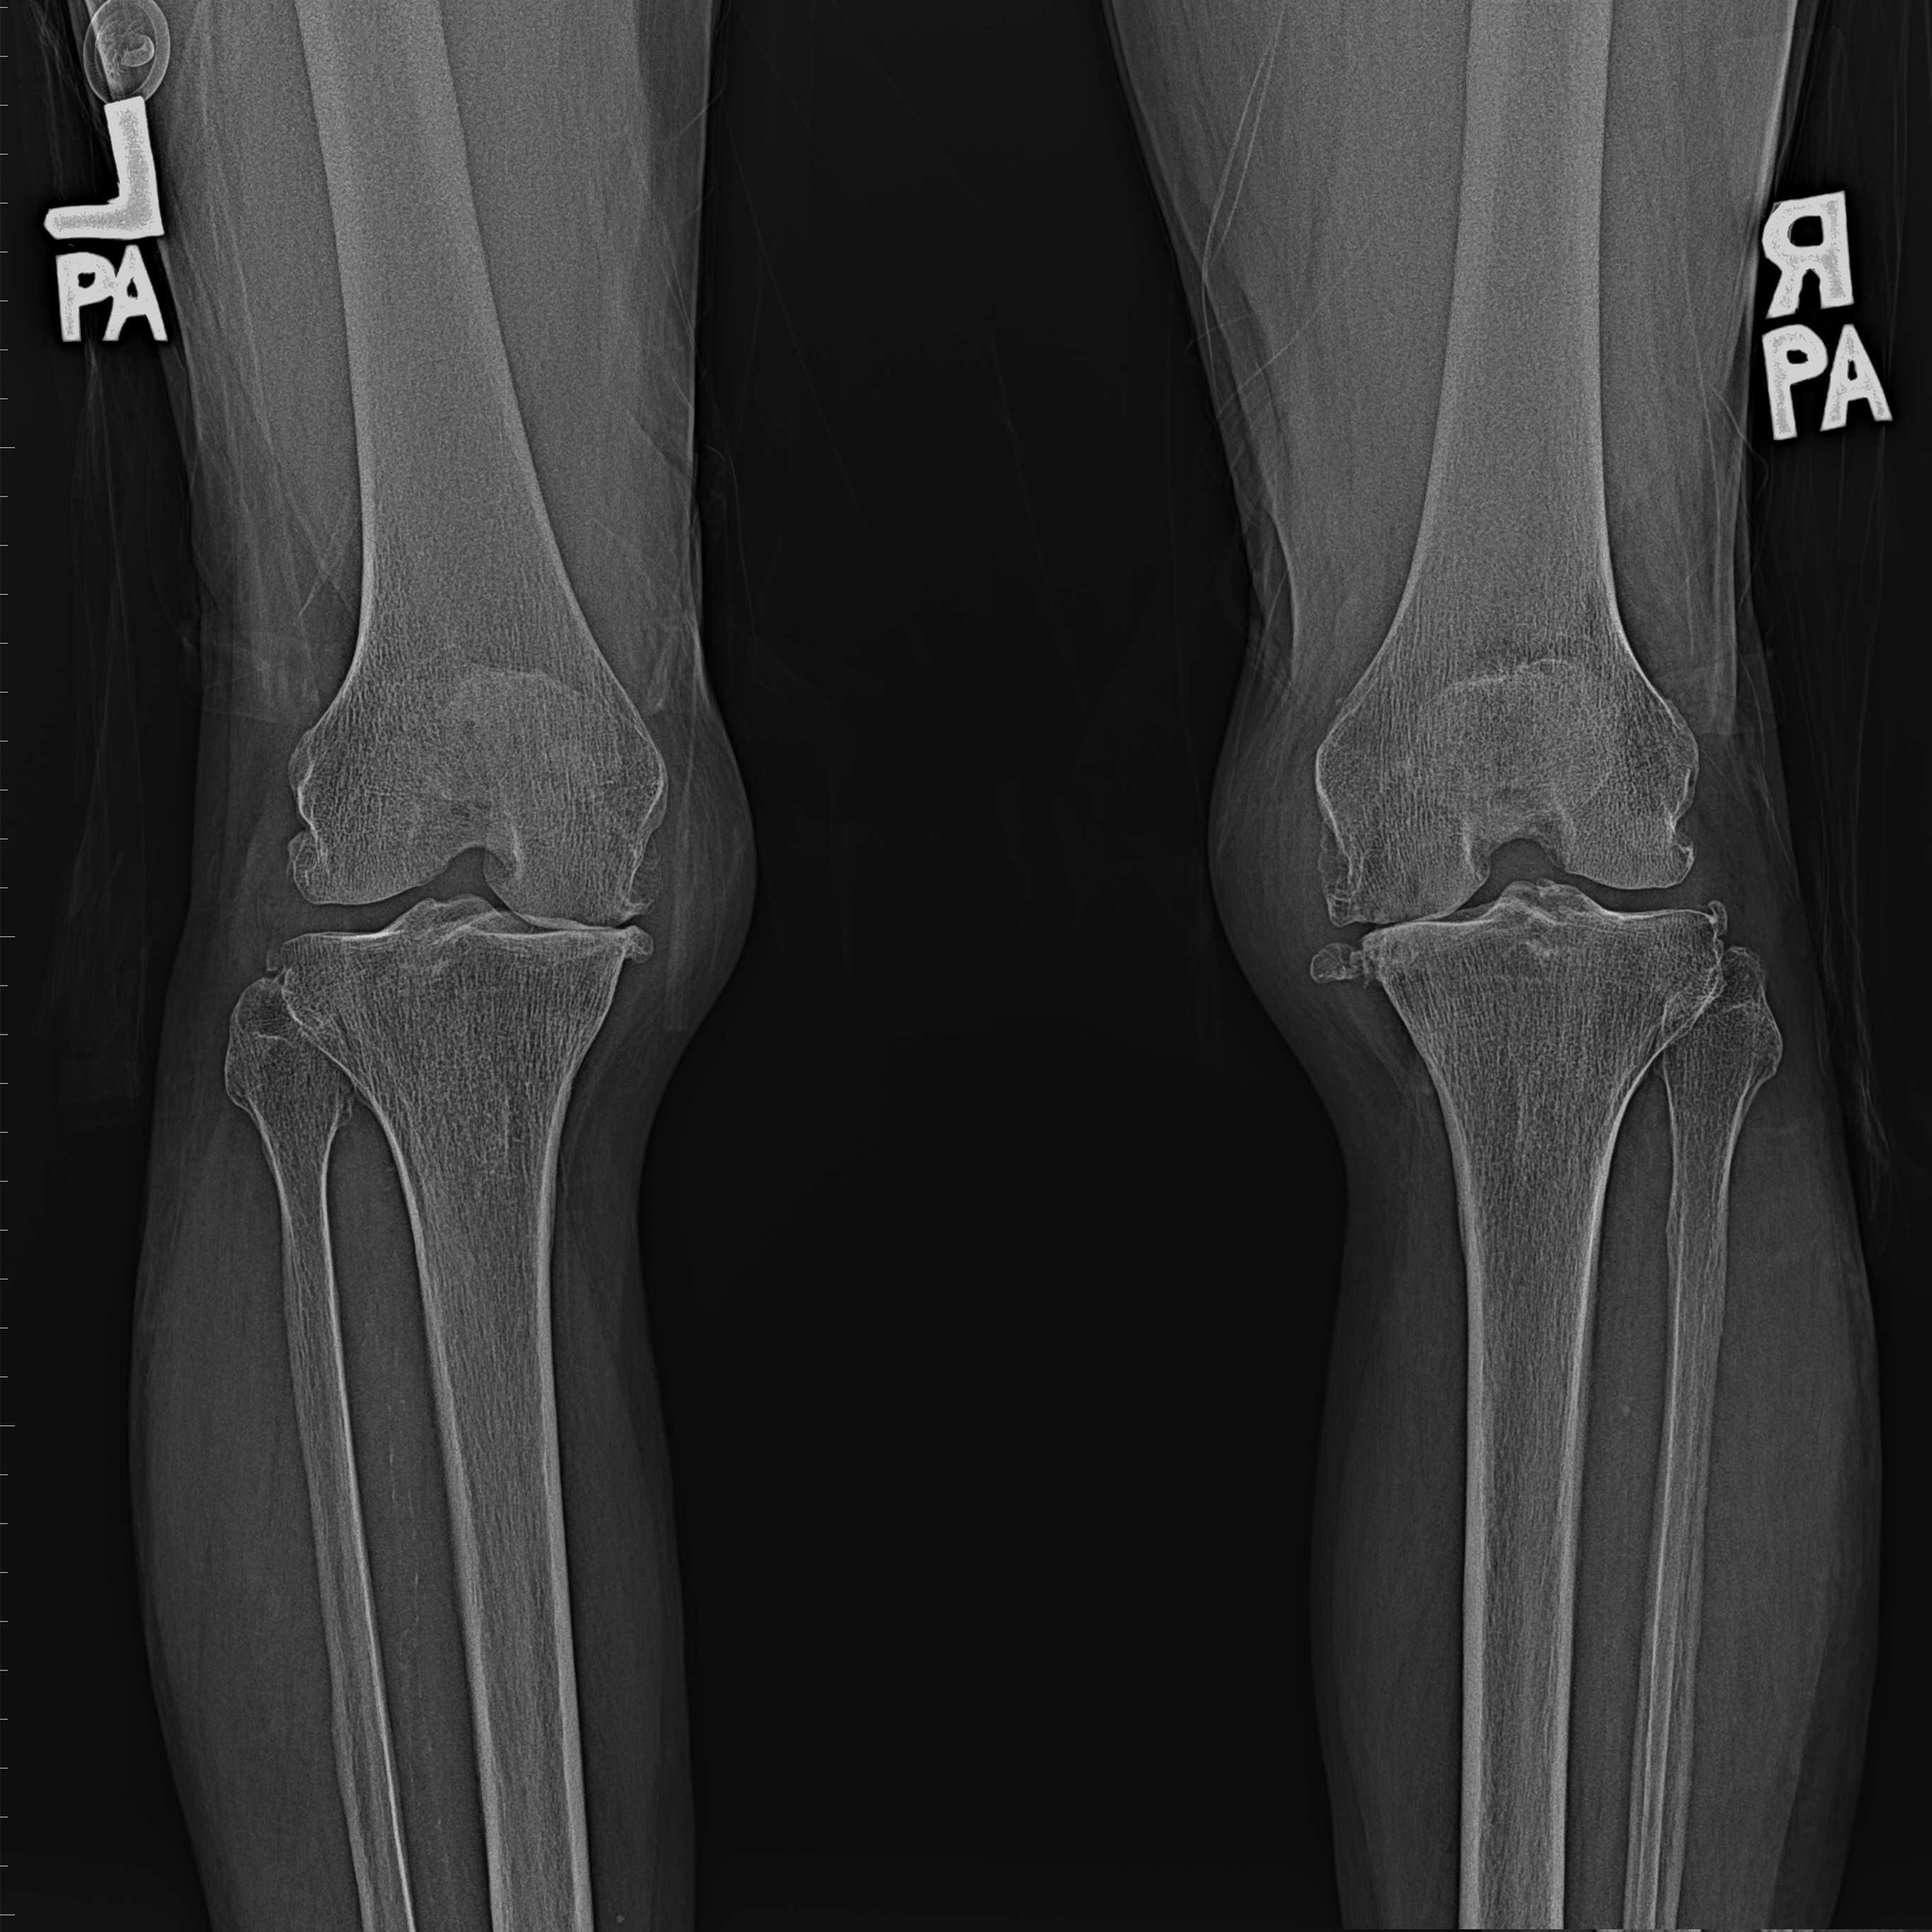

機器手臂手術 首頁 案例分享 膝關節手術 機器手臂手術 蔡女士 78歲 術前 術後 陳女士 70歲 術前 術後 術前 術後 ANGEVINE女士 73歲 術前 術後 U.S.A Mark 73歲 術前 術後 藍女士 78歲 術前 術後